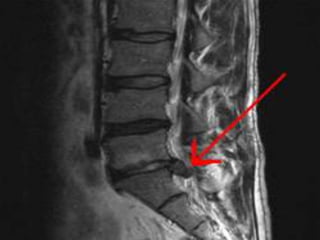

X-Ray : lumbo-sacral spine;

 Narrowed disc spaces.

 Loss of lumber lordosis.

 Compensatory scoliosis.

CT scan lumber spine;

 It can show the shape and size of the spinal canal, its contents, and the

structures around it, including soft tissues.

 Bulging out disc.

MRI lumber spine;

 Intervertebral disc protrusion.

 Compression of nerve root.

Myelogram;

 pressure on the spinal cord or nerves, such as herniated discs, tumors,

or bone spurs.